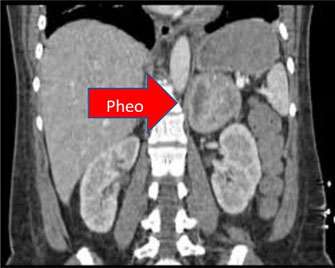

R. pheo, Liver >

Larger image >